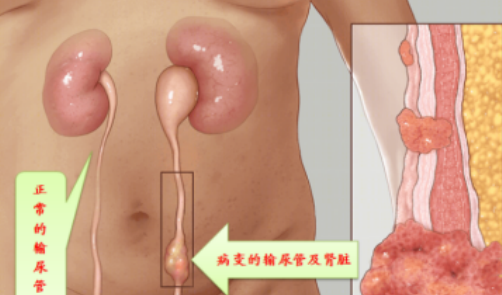

(5)肿瘤

输尿管周围的肿瘤,如输尿管肿瘤、膀胱癌、直肠癌等,可能侵犯输尿管壁,导致输尿管狭窄。

输尿管狭窄是指输尿管管腔的局限性缩窄,导致尿液引流不畅,引起肾积水和肾功能损害。输尿管狭窄可发生在输尿管的任何部位,常见于肾盂输尿管连接部、输尿管中段和输尿管膀胱连接部。输尿管狭窄的程度和长度各不相同,轻者可能仅表现为输尿管轻度扩张和肾积水,重者可导致完全性梗阻和肾功能丧失。